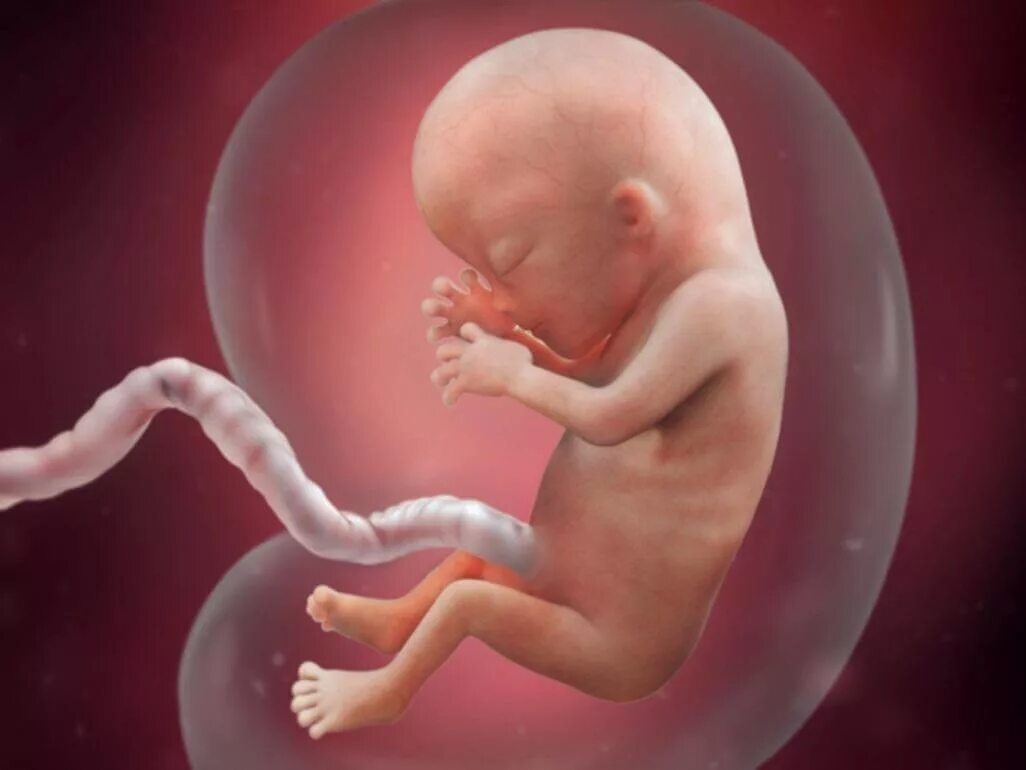

Ребенок в 13 недель